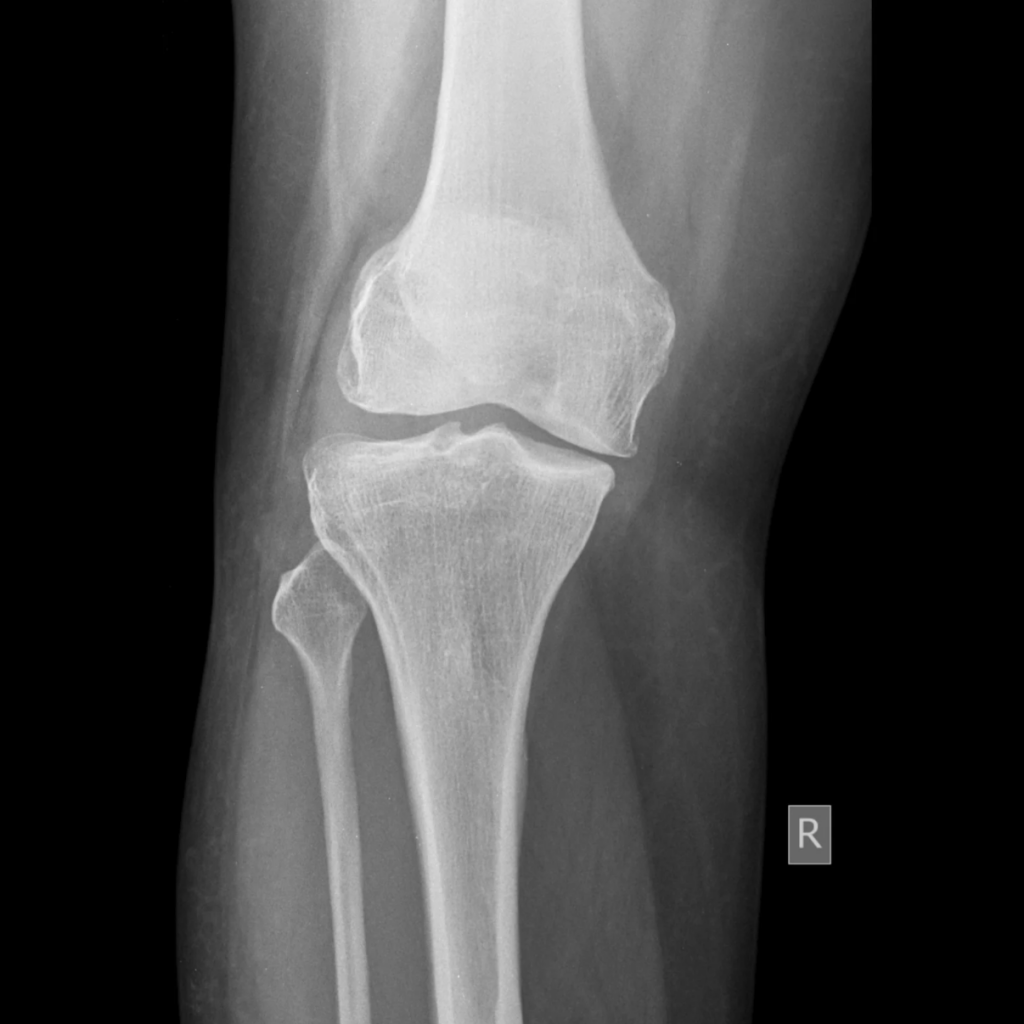

レントゲン検査は、体の様子を写真に撮る検査です。目では見えない骨や関節の状態を、X線という光を使って確認します。

レントゲン検査は「骨の輪郭がハッキリ見える」という特徴があります。

MRI検査をすると、たとえばレントゲンでは見えない膝の半月板などの柔らかい組織が見えます。